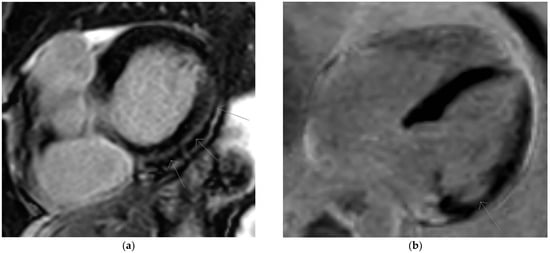

The diagnosis of CS was suspected, based on the recent history of ventricular arrhythmia and sinus arrest in the absence of echocardiographic structural heart disease and hemodynamically significant myocardial ischemia. Laboratory results showed normal inflammatory parameters and normal troponin levels. The patient was admitted for device explantation, performance of cardiac magnetic resonance (CMR), diagnostic invasive electrophysiologic study and upgrade to a dual chamber implantable cardioverter defibrillator. During electrophysiologic study, sustained ventricular tachycardia could be induced. CMR showed prolonged myocardial relaxation up to 62–64 msec on T2 mapping in the inferolateral basal segment of the left ventricle, suggesting acute myocardial inflammation In addition, midmyocardial and subepicardial late gadolinium enhancement (LGE) was demonstrated in the same inferolateral basal segment of the left ventricle (Figure 3 and Figure 4).

Figure 3.

Cardiac magnetic resonance. (a,b) Late gadolinium enhancement (LGE) inferolateral basal midmyocardial and subepicardial (arrows) in two chamber and four chamber views.